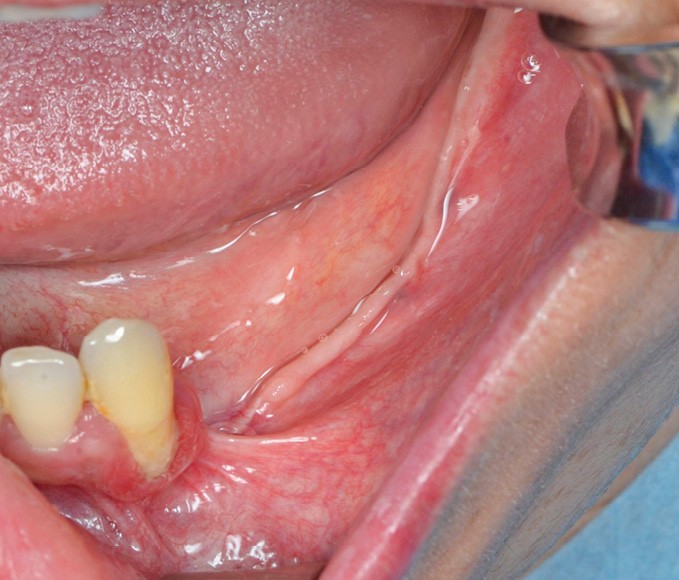

Il s’agit d’une jeune patiente 38 ans ayant présenté une perte osseuse à la suite de péri-implantite. Les implants ont été déposés. La patiente présente une atrophie mandibulaire postérieure classée Cawood V (fig. 1).

L’edentement est important de 33 à 38 et implique un prélèvement de grande étendue (fig. 2).

Après injection du produit anesthésique, l’incision est étendue de la 33 au trigone rétromolaire. Une incision de décharge est réalisée en distal de 33 et dans le trigone en direction de la ligne oblique externe.

Le décollement muco-périosté est amorcé au syndesmotome faucille puis à la rugine d’Obwegeser.

Le nerf mentonnier est exposé (fig. 3).